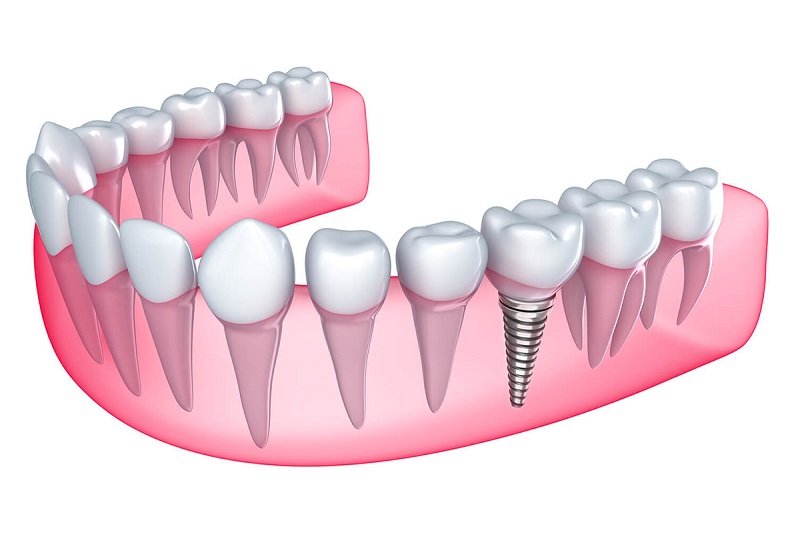

Mất răng lâu năm hoàn toàn có thể trồng lại được bằng phương pháp cấy ghép Implant. Mặc dù tình trạng mất răng kéo dài có thể ảnh hưởng đến xương hàm và cấu trúc răng miệng, nhưng với sự tiến bộ trong công nghệ nha khoa, bác sĩ có thể thực hiện cấy ghép Implant hiệu quả. Quá trình này không chỉ phục hồi chức năng ăn nhai mà còn cải thiện thẩm mỹ, giúp người bệnh tự tin hơn trong giao tiếp. Tuy nhiên, trước khi thực hiện, cần đánh giá tình trạng sức khỏe và xương hàm để đảm bảo thành công của ca phẫu thuật.

Cấy ghép Implant là phương pháp phục hình răng mất rất hiệu quả, giúp tái tạo cả chân răng và thân răng. Với một trụ titanium được cấy vào xương hàm, Implant sẽ hoạt động như một chân răng tự nhiên, mang lại cảm giác vững chắc và ổn định. Không chỉ phục hồi hình dáng của răng, phương pháp này còn giúp duy trì cấu trúc hàm, ngăn chặn tình trạng biến dạng khuôn mặt do mất răng.

Một trong những vấn đề nghiêm trọng do mất răng lâu năm là hiện tượng tiêu xương hàm. Khi không còn răng, xương hàm sẽ không nhận được áp lực cần thiết trong quá trình nhai, dẫn đến việc xương dần tiêu biến theo thời gian. Cấy ghép Implant giúp duy trì kích thước và mật độ xương hàm, ngăn chặn tình trạng tiêu xương và tụt lợi, từ đó bảo vệ sức khỏe răng miệng lâu dài.

Khác với những phương pháp phục hồi khác như cầu răng sứ, cấy ghép Implant không yêu cầu mài sửa các răng bên cạnh. Điều này giúp bảo tồn tối đa các răng tự nhiên còn lại, tránh làm tổn thương đến chúng. Việc cấy ghép chỉ tác động đến vị trí mất răng, giữ cho các răng xung quanh vẫn khỏe mạnh và ổn định, tạo điều kiện cho một hàm răng bền vững và khỏe mạnh.

Một trong những lợi ích lớn nhất của việc trồng Implant là khả năng tái tạo cảm giác nhai tự nhiên. Các trụ Implant được thiết kế để chịu lực tương tự như răng thật, giúp người bệnh có thể ăn uống thoải mái mà không lo lắng về việc răng giả bị lỏng lẻo hay không đủ sức nhai. Điều này không chỉ mang lại sự tiện lợi trong sinh hoạt hàng ngày mà còn giúp cải thiện chất lượng cuộc sống.